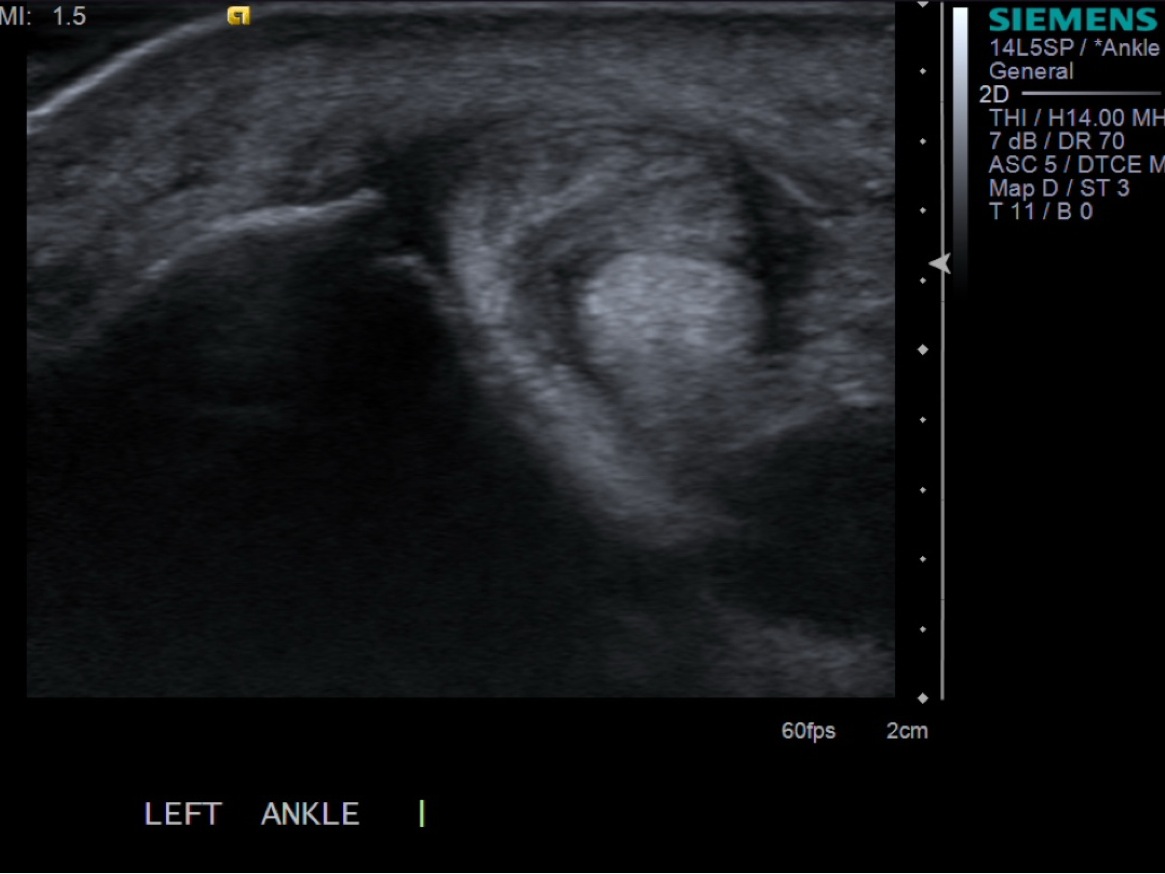

3. Place probe in short axis over the peroneal tendon sheath.